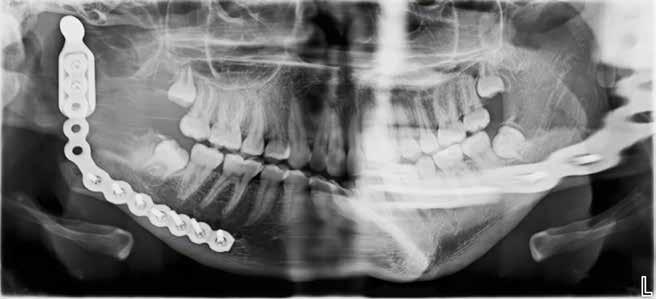

overbid (VOB). Papillen mellem 1+1 er betydeligt reduceret pga. fæstetab, og de mesialt kippede 1+1 har resulteret i en ”dark triangle”. Den facioorale funktion er for nuværende i.a. Panoramarøntgen (Fig. 1, I) viser marginalt knogletab i begge kæber og fravær af 8,7+7,8 og 8,7-8.

Objektivt anbefales behandling af det dybe bid, som ubehandlet forventes at forværres yderligere over tid. Patienten har ønske om behandling med æstetisk ortodontisk apparatur, alignere, og det vurderes muligt at behandle malokklusionen med alignere. Dog anbefales det generelt, at alignere undgås eller benyttes med væsentlige modifikationer af alignerens retention ved tandmobilitet, da dette ellers kan medføre jiggling, når aligneren tages af og på mange gange dagligt. På den anden side er der nogen evidens for, at alignerbehandling er associeret med bedre renhold og parodontal sundhed sammenlignet med fast apparatur (16).

Der planlægges alignerbehandling af begge kæber med intrusion af 1+1 og 2,1-1,2, nivellering af trangstilling UK med interproksimal reduktion (IPR) (Fig. 2 A, B) og senere IPR OK for reduktion af dark triangles mellem incisiverne efter nivellering. Patienten instrueres i at benytte alignere 20-22 timer/ dag med alignerskift hver 7. dag, og patienten ses hver 3.-8. uge under forløbet. Den første alignerserie består af 16 alignere for nivellering OK/UK og IPR i UK (Fig. 2). Efter denne serie planlægges IPR mellem incisiverne i OK for reduktion af dark triangles (Fig. 3) samt yderligere intrusion af OK og UK-fronten i 12 refinement-alignere. Patienten udviser god kooperation og er meget tilfreds med alignerapparaturet, som er mindre synligt end det faste apparatur (Fig. 4).

Behandlingen afsluttes med yderligere refinement-alignere for finindstilling af okklusionen, og efter 11 måneders ortodontisk behandling er der opnået normale relationer i alle tre